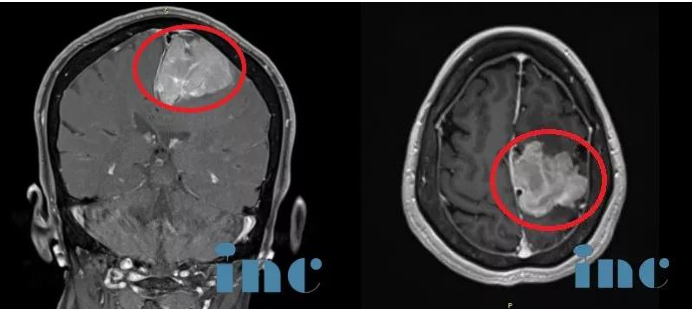

原来,经核磁共振检查,医生发现了张师傅颅内出现一个直径超过6cm的较大占位,根据医生初步判断,很可能是脑膜瘤。由于肿瘤侵犯前颅底及大脑镰,与同侧大脑前动脉粘连紧密,而这个区域的大脑血供异常丰富,这给瘤体手术摘除带来了较大的难度和风险。经过手术,患者颅内的较大肿瘤被成功摘除,粘连大脑前动脉保护完好。患者术后恢复良好。手术后,张师傅消失已久的笑容又重新回到了脸上,面对家人他终于不再沉默,也爱说话了。

术前MR:脑膜瘤钙化和瘤周压迫、水肿效应明显,且已侵袭矢状窦,压迫运动功能区